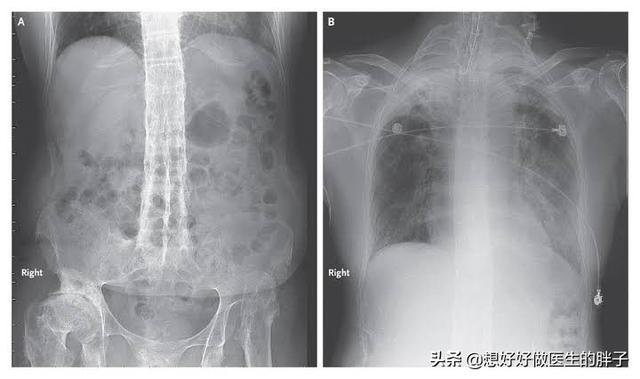

强直性脊柱炎属于风湿免疫科的疾病。具体的原因到现在也不是非常的明确。这种疾病主要累及骶髂关节、脊柱以及一些大的关节。病变的部位会发生比较严重的纤维化、骨化。患者出现疼痛以及日渐加重的活动受限。

强直性脊柱炎中晚期脊柱活动受限。检查x线可以发现典型的竹节样改变。诊断往往不难。早期诊断却容易和腰疼混淆。导致遗漏。早期的强直性脊柱炎患者以下的一些特点:

强直性脊柱炎是一种严重危害人类健康的风湿免疫性疾病。是一种是以骶髂关节和脊柱附着点炎症为主要症状的疾病。主要影响脊柱、胸腔和骨盆的关节。这几处的关节会生长粘连在一起。时间长了。脊柱就会失去灵活性。

强直性脊柱炎的可怕之处不仅仅是发作起来疼的要死。严重影响生活质量。更可怕的是病情控制不佳的话。晚期可发生脊柱畸形和关节强直。致残和致死风险增高的同时。